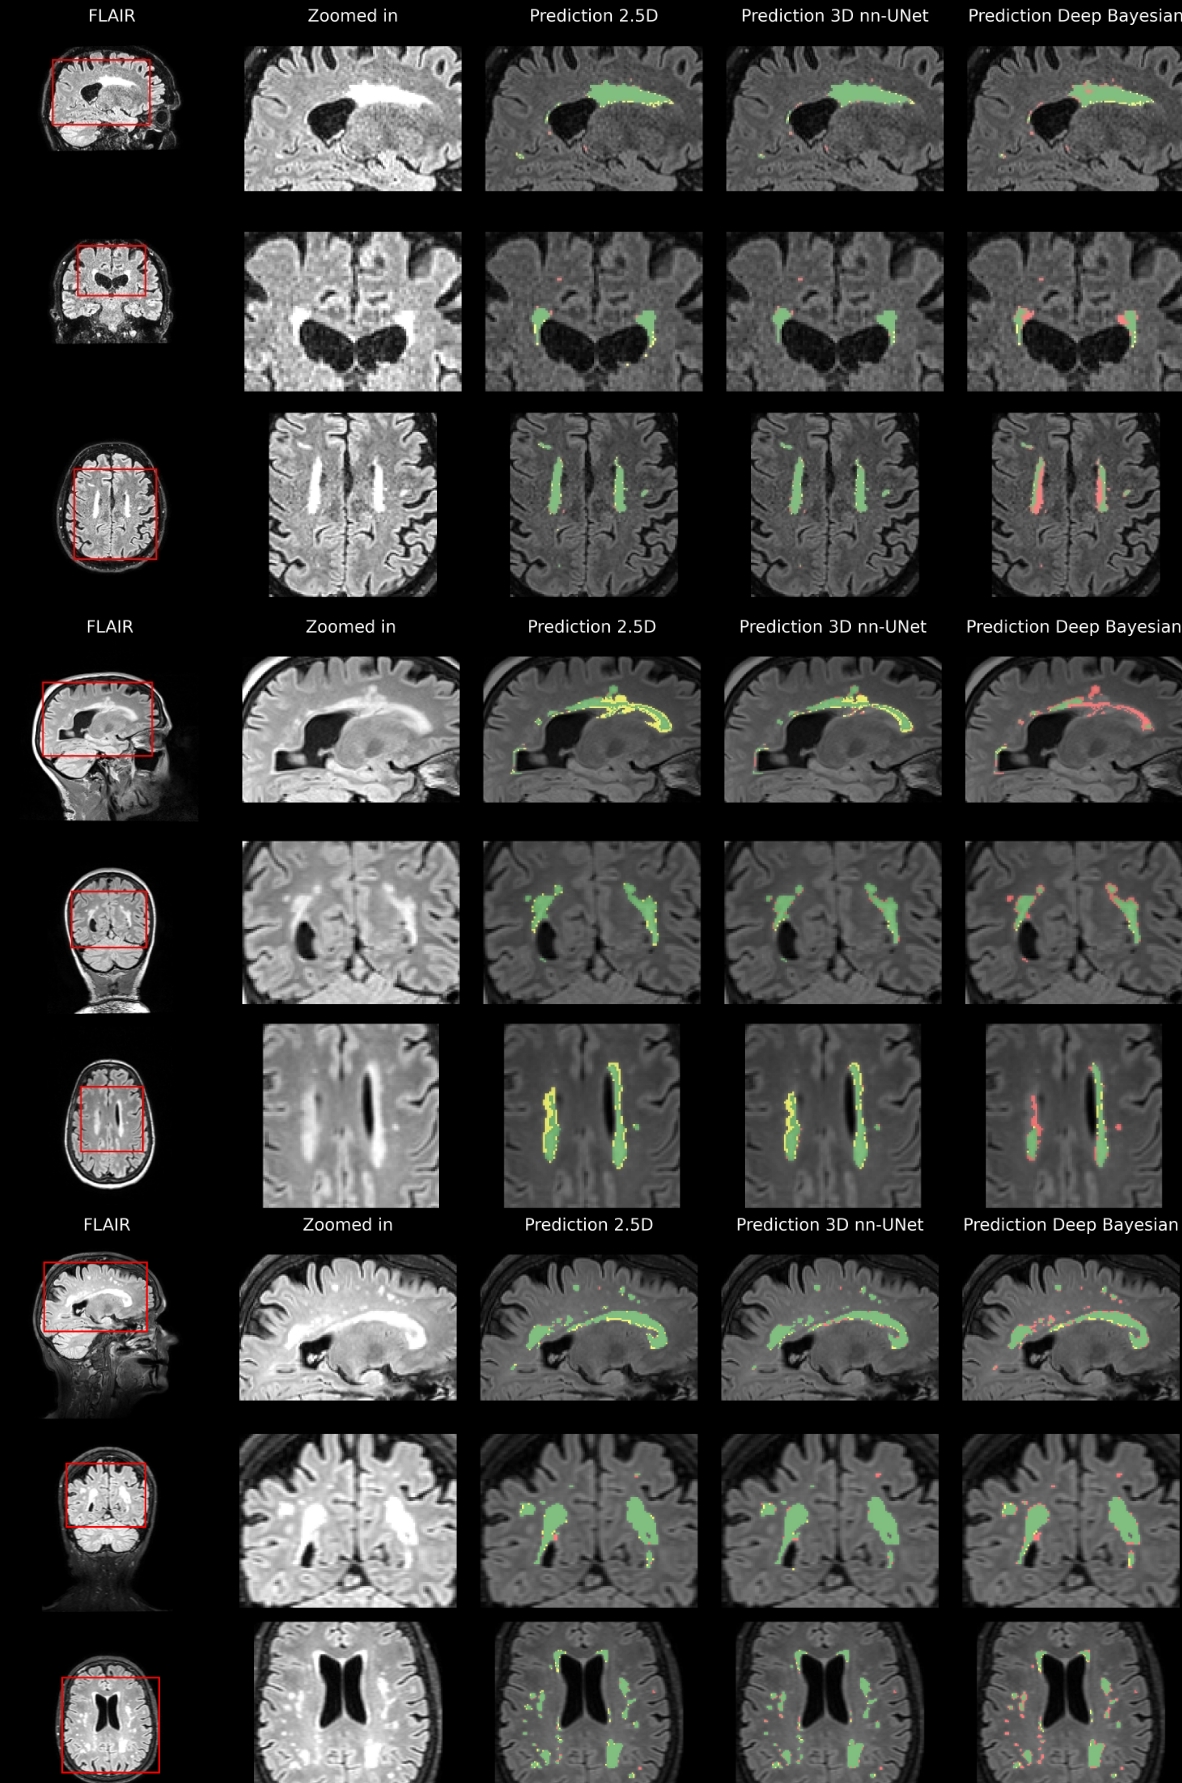

Fig 8 shows sample cases of segmentation performance for all three models for three different participants in the internal test set. Here, the yellow color denotes over-segmentation, the red color denotes under-segmentation, and the green color denotes correct segmentation.

Large lesions appear to be detected with a high level of ground truth overlap. There seems to be more uncertainty, especially for the 2.5D and Deep Bayesian where the lesions are more smudged out. Fig 9 shows the example segmentation from three different participants in the external test dataset for the three different models.

Refer to caption

Figure 8: Internal test data results. Predictions based on internal test data overlayed on FLAIR for three participants. The first column shows three slices from each orientation for three different participants. The second column shows a zoomed-in view of an area of interest. The last columns show the segmentation results for the three different models. Green shows true positive voxels, red shows false negatives, and yellow shows false positives.